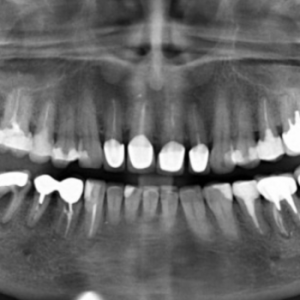

Рентгенологічне дослідження зубів – це високоефективний метод діагностики, який дозволяє лікарям визначити наявність або відсутність стоматологічних захворювань, спланувати лікування і перевірити якість таких процедур, як пломбування кореневих каналів або встановлення імплантатів.

В основі методу лежить використання рентгенівського апарату, призначеного для дослідження внутрішніх структур зубів і тканин порожнини рота. Завдяки променю, що проектує зображення, лікар може виявити порожнини, карієс, зміни типу та складу тканин у досліджуваній ділянці тощо. Залежно від потреби, можна зробити рентген всіх зубів або кожного зуба окремо.

Рентген зубів – один з найпоширеніших методів діагностики в сучасній стоматології. Його призначають у процесі діагностики більшості проблем, від каріозних уражень і флюсу до виявлення утворення кіст і контролю якості пломбування кореневих каналів.

Під час первинного огляду пацієнта стоматолог може визначити причину дискомфорту або болю лише за зовнішніми ознаками та симптомами. Більшість складних стоматологічних проблем зачіпають як поверхні зубів, так і внутрішні тканини зубів, ясен і щелепної кістки. Для постановки точного діагнозу лікарю необхідно отримати актуальні знімки тканин у проблемній ділянці (одного, кількох або всієї щелепи).